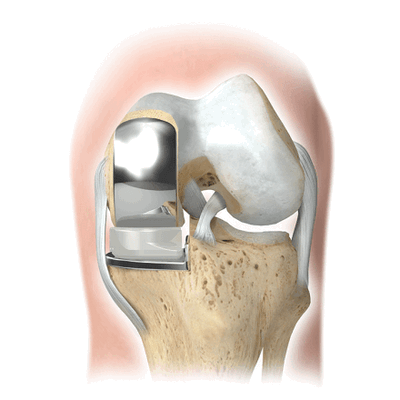

Если сустав поражен указанным на изображении образом, то возможна его частичная замена.

Основной метод лечения - постановка эндопротеза вместо поврежденного сустава. Раньше выполнялось преимущественно тотальное эндопротезирование коленного сустава, однако сейчас активно развивается другое направление - одномыщелковое (частичное) эндопротезирование.

Упрощенная схема установки импланта.